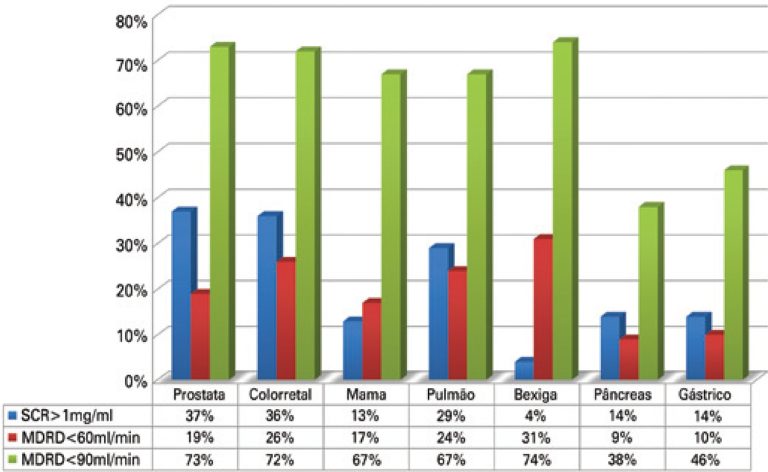

DOI: 10.1590/S1679-45082014AO3003

Objective To estimate the prevalence of abnormal glomerular filtration rate in elderly patients with solid tumors. Methods A retrospective study with patients aged >65 years diagnosed with solid tumors between January 2007 and December 2011 in a cancer center. The following data were collected: sex, age, serum creatinine at the time of diagnosis and type of tumor. Renal function was calculated using abbreviated Modification of Diet in Renal Disease (MDRD) formulae and then staged in accordance with the clinical practice […]

Keywords: Aged; Glomerular filtration rate; Neoplasms; Prevalence; Renal insufficiency